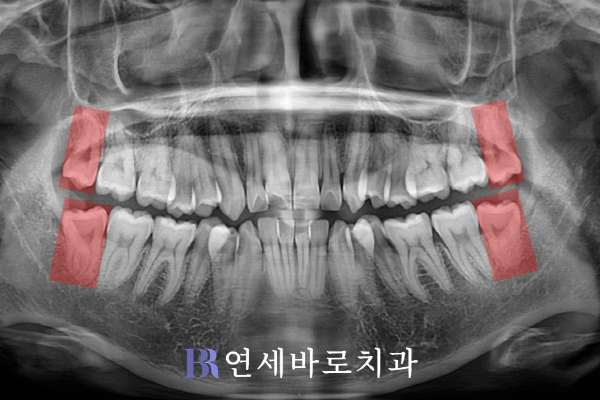

해당 환자분의 경우에는

사랑니 4개를 모두 제거하고,

추가로 소구치 4곳을 발치하여

적절한 공간을 만들었습니다.

이후에 덧니를 고르게 배열하고,

남은 공간을 적절하게 활용하여

전치부의 후방이동을 도모했습니다.

장치는 인비절라인을 활용했으며,

위 사진은 올해 5월에 찍었습니다.

악궁 형태가 U자형의 아치로

바로잡히기 시작했습니다.

치아를 충분히 움직여줌으로써

발치공간을 닫아주었습니다.

아랫니에서는 발치로 확보한

공간이 완전히 폐쇄되었습니다.

중심선이 맞춰지기 시작했으며,

앞으로 뻗은 윗니와 아랫니의

각도도 성공적으로 조절되어가는

양상을 확인해볼 수 있었습니다.

어금니도 위아래를 서로 엇갈리게

교차할 수 있도록 만들었습니다.